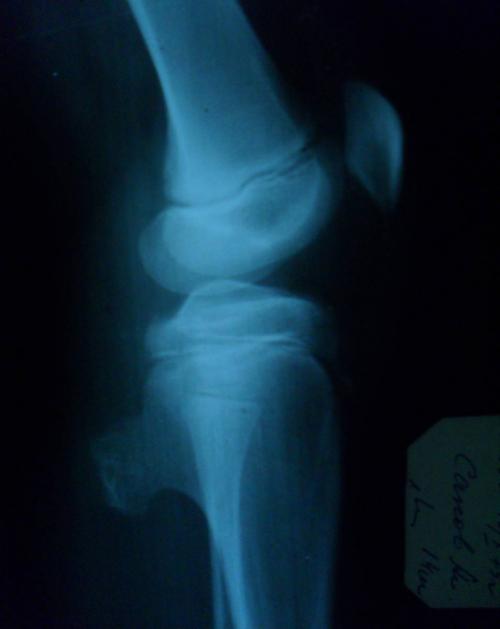

Опухоль кости, возникающая из костной ткани, склонная к бурному течению, быстрому образованию метастазов. Развивается преимущественно в возрасте 10-30 лет, мужчины страдают вдвое чаще женщин. Обычно локализуется в метаэпифизах костей нижних конечностей, в 50% случаев поражает бедро, затем следуют большеберцовая, малоберцовая, плечевая, локтевая кости, кости плечевого пояса и таза. На начальных стадиях проявляется тупыми неясными болями. Затем метаэпифизарный конец кости утолщается, ткани становятся пастозными, образуется видимая венозная сеть, формируются контрактуры, боли усиливаются, становятся невыносимыми.

На рентгенограммах бедра , голени и других пораженных костей на начальных стадиях выявляется очаг остеопороза со смазанными контурами. В последующем образуется дефект костной ткани, определяется веретенообразное вздутие надкостницы и игольчатый периостит . Лечение – оперативное удаление опухоли. Раньше применяли ампутации и экзартикуляции , теперь чаще выполняют органосохраняющие операции на фоне пред- и послеоперационной химиотерапии . Дефект кости замещают аллопротезом, имплантатом из металла или пластика. Пятилетняя выживаемость – примерно 70% при локализованных опухолях.

Проявляется интенсивными болями, затруднением движений в прилегающем суставе и отечностью мягких тканей. При расположении в позвонках развивается пояснично-крестцовый радикулит . Течение обычно медленное. На рентгенограммах обнаруживается очаг деструкции. Кортикальный слой разрушен, периостальные наложения выражены нерезко, имеют вид спикул или козырька. Для уточнения диагноза могут назначаться МРТ, КТ, остеосцинтиграфия , открытая и проникающая игольчатая биопсия. Лечение чаще комплексное – химиохирургическое или радиохирургическое.

Для уточнения диагноза может назначаться рентгенография , КТ, МРТ, позитронно-эмиссионная томография , ангиография , остеосцинтиграфия, УЗИ, трепанобиопсия , биопсия опухоли, молекулярно-генетическое и иммуногистохимическое исследования. На рентгеновских снимках определяется зона с участками деструкции и остеосклероза. Кортикальный слой нечеткий, расслоен и разволокнен. Выявляется игольчатый периостит и выраженный мягкотканный компонент с однородной структурой.